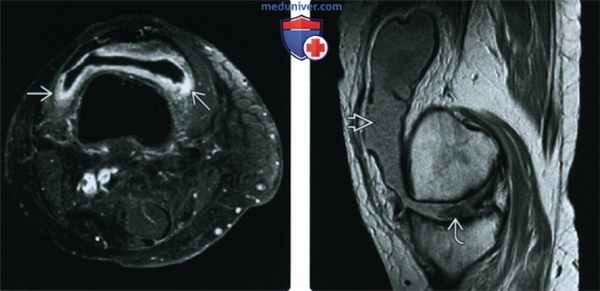

3. МРТ при ревматоидном артрите коленного сустава:

• Режим Т1:

о Выпот и подколенная киста (сигнал низкой интенсивности)

о Эрозии, субхондральные кисты, отек костного мозга характеризуются сигналом низкой интенсивности

о Линии патологических переломов (низкоинтенсивный сигнал)

• Последовательности, чувствительные к жидкости:

о Выпот, характеризующийся сигналом высокой интенсивности окружен утолщенной синовиальной оболочкой, имеющей сигнал низкой интенсивности

о Подколенная киста имеет сигнал высокой интенсивности:

- Идентифицируется в икроножно-полуперепончатой сумке, распространяется проксимально или дистально

- Разорванная киста: менее четкий сигнал высокой интенсивности, окружена отечными мягкими тканями; часто имеет шейку, демонстрирующую исходную локализацию

о Хрящ визуализируется непосредственно, особенно в последовательностях с подавлением сигнала от жира, которые демонстрируют различный сигнал, обусловленный выпотом

о Отек костного мозга (сигнал высокой интенсивности)

о Эрозии и субхондральные кисты имеют сигнал высокой интенсивности

о Линии патологических переломов характеризуются сигналом высокой интенсивности

о Хорошо визуализируются повреждения связок и сухожилий:

- Четырехглавая мышца подвержена риску повреждения при РА

о Последовательности, взвешенные по протонной плотности: сопутствующие повреждения менисков

• Режим Т1, с контрастированием, с подавлением сигнала от жира:

о Интенсивно контрастируемая синовиальная оболочка, окружающая выпот и подколенную кисту (сигнал низкой интенсивности)

о Контрастируемые костные края вокруг жидкости в эрозиях и субхондральных кистах (сигнал низкой интенсивности)